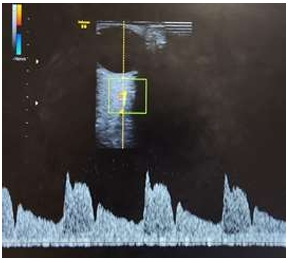

Assinale a alternativa CORRETA que representa a imagem de maior risco para pré-eclâmpsia, considerando as

pacientes com mesmo quadro clínico e obstétrico.